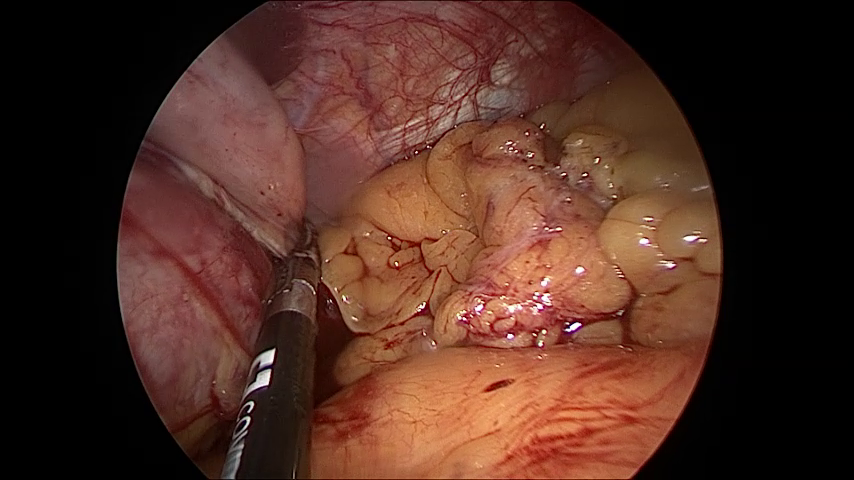

(a) Similarity of frames within different surgery types

Figure 5: Challenges associated with Laparo425 dataset